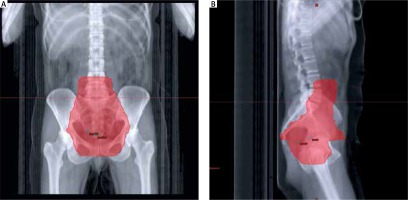

The study group consisted of 52 patients with cervical squamous cell carcinoma staged IIB (n = 39) and IIIB (n = 13) treated at the Department of Teleradiotherapy, Copernicus Memorial Hospital of Lodz in 2015-2017. Detailed clinical data of the studied population are presented in Table 1. Staging was evaluated clinically based on a pelvic magnetic resonance imaging (MRI) scan. The treatment scheme involved teleradiotherapy to the pelvis, uterus, both adnexa and regional lymph nodes (Fig. 1A, B) up to a dose of 44 Gy fractionated at 2 Gy with weekly injections of cisplatin at a dose of 40 mg/m2. In patients with contraindications to chemotherapy only teleradiotherapy was applied. After teleradiotherapy with or without chemotherapy was completed, high-dose-rate (HDR) brachytherapy was implemented, fractionated at 7 Gy weekly for four weeks up to a total dose of 28 Gy, or teleradiotherapy was continued up to a total dose of 60 Gy. Follow-up appointments after treatment were carried out in the oncological outpatient clinic. Serum SCC-Ag concentration was assessed prior to radiotherapy and four weeks after the end of treatment.